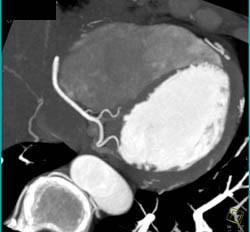

3D and MPR Sequence of Right Coronary Artery (RCA)